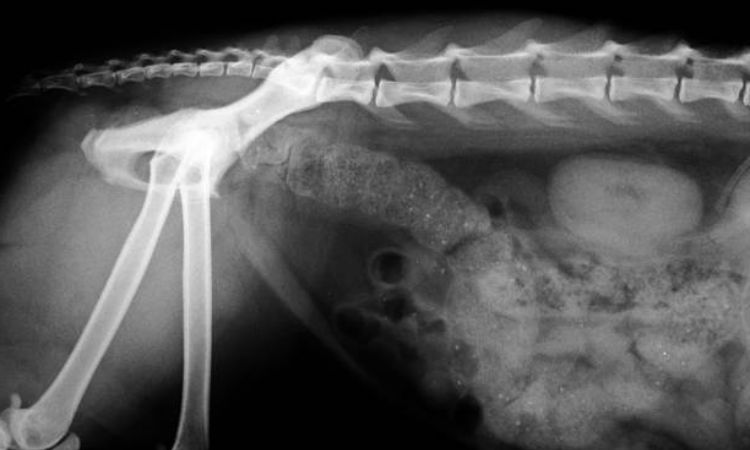

Stress is another often-overlooked factor. Changes in the home environment, conflict with other pets, loud noises, or an unclean litter box can cause cats to delay using the box. Over time, this stool retention can result in constipation. In some cases, constipation is linked to underlying medical conditions such as kidney disease, neurological disorders, or megacolon—a condition in which the colon becomes enlarged and loses its ability to move stool effectively.

- Chronic or recurring constipation that may indicate megacolon or another underlying medical condition.